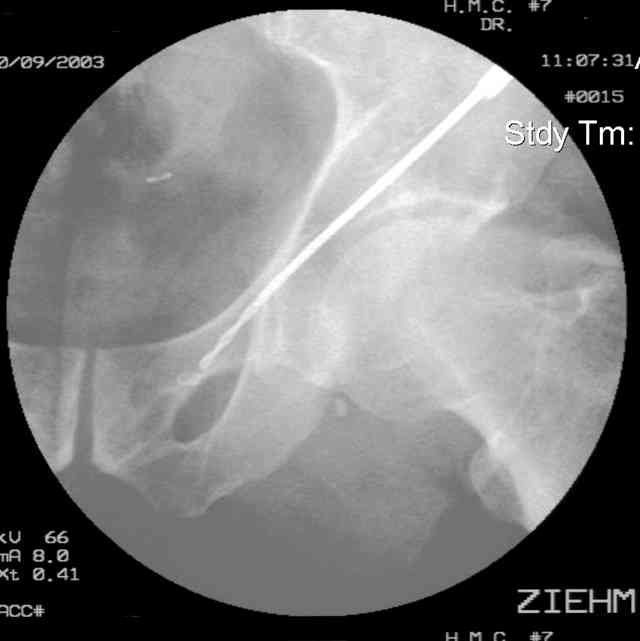

Here's a pic from the foot of the bed and you can see the clamp in the wound and the knee is extended so he must've had a tight rectus. The C-arm is rolled back to an obturator oblique image to reveal the anterior column...we put a slight outlet tilt to combine the images and give a better view of the anterior column...we can see the posterior column limb reduction in the wound, we can palpate the quadrilateral surface limb, and the image demonstrates the anterior column portion...you can adjust the tilt and rotation to image tangentially to the fracture plane if you'd like. We've inserted a 2mm K wire to site the starting point and aim/orientation for the drill and screw

Prone Imaging

same image, just another look.